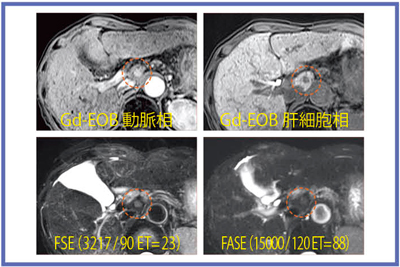

3Tではノイズの多さからFASEを使いたくなるが,図7のHCC症例のように,FASEのコントラストが十分でない場合もある。逆に,肝嚢胞と肝血管腫のように,FSEでは信号差が少なく,FASEでは嚢胞が著明な高信号を示す場合もあり(図8),現状ではFSEとFASEの両方の撮像が望ましいと考える。

図7 早期濃染するHCC症例

FASEでの腫瘍コントラストは,FSEよりも 不明瞭である。